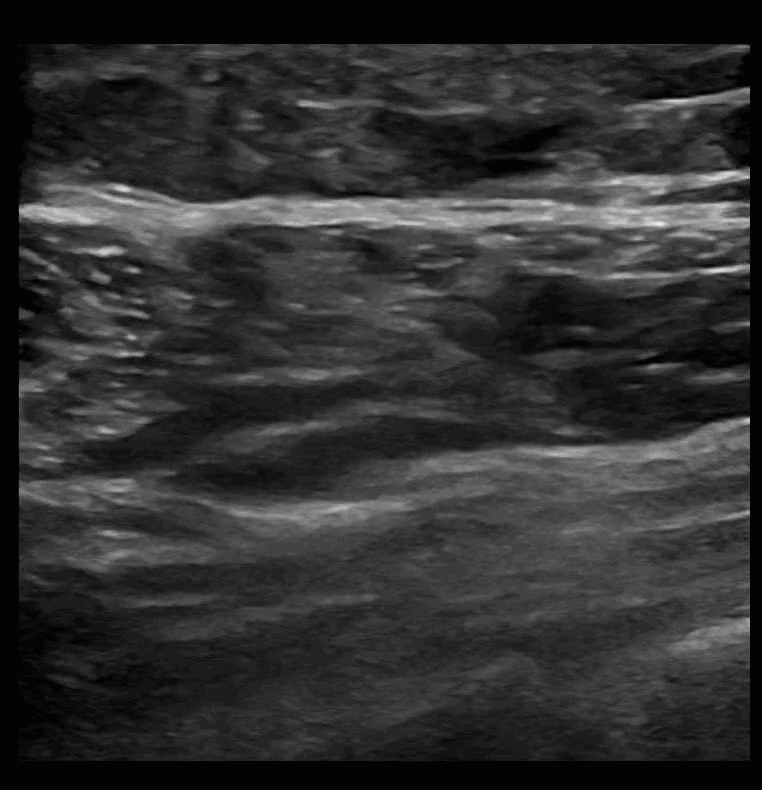

SAPB 1: Pre-scan. The latissimus dorsi muscle comes to a point on the right of the screen as you scan posterior to anterior. Just deep to the latissimus dorsi muscle is the serratus anterior muscle. Deep to the serratus anterior muscle is the rib and pleura.